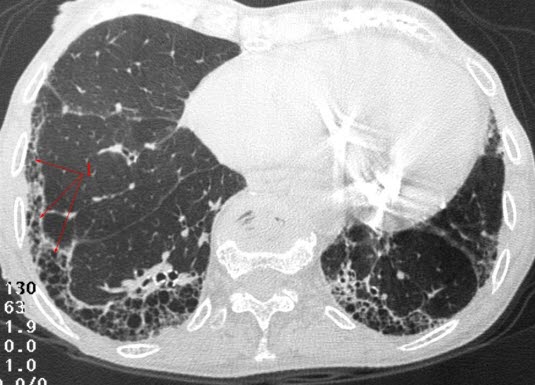

Lungefibrose (HRCT)Lungefibrose er en tilstand med betennelse og økt mengde bindevev (arrvev) i lungene. Arrdannelse er kroppens måte å reparere vevsskade på, ikke bare i lungene, men i hele kroppen. Det er sammenlignbart med et arr i huden etter et skrubbsår. Ved lungefibrose er det unormal arrdannelse i lungeblærene. Når det dannes arr isteden for normalt lungevev, blir gassutvekslingen mellom lunge og blod dårligere enn normalt. Lungene blir stivere og mindre bevegelige, og det arealet som kan brukes til gassutveksling, minker. Har man lett grad av lungefibrose, er det ikke sikkert man merker det på pusten, men jo mer fibrose som dannes, jo tyngre blir det å puste.